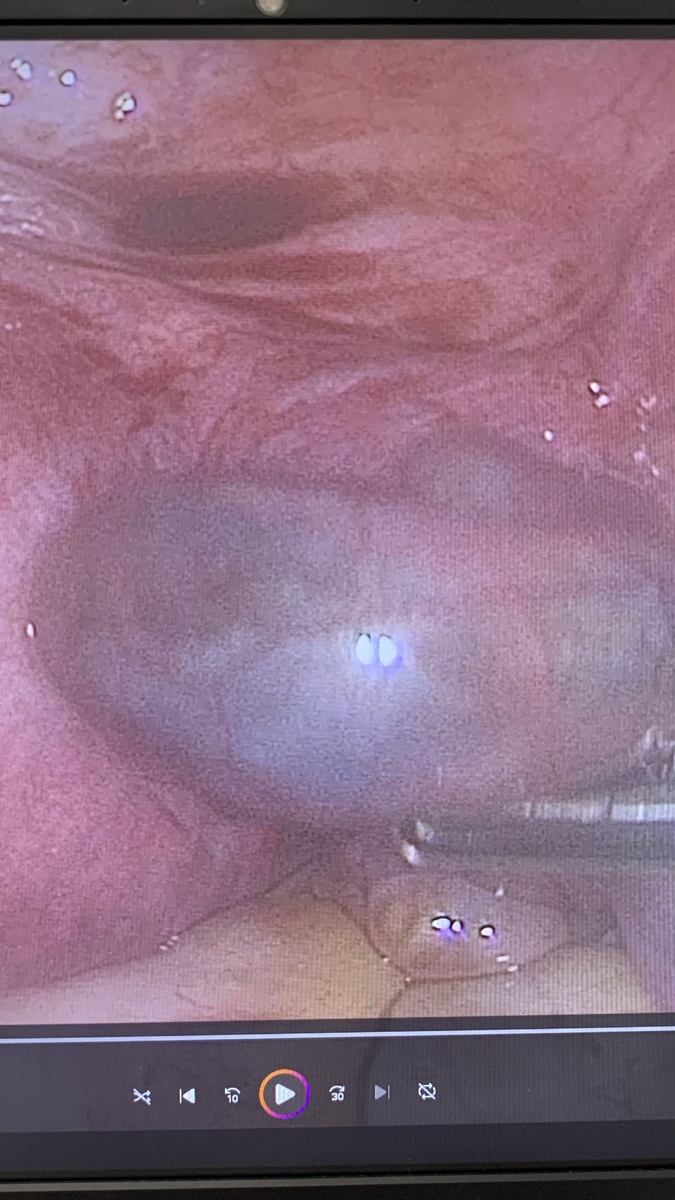

Внематочная беременность: 1 фото и 2 фото - беременность в маточной трубе; 3 фото - беременность в яичнике (очень редко встречается); 4 фото - беременность в углу матки (редко встречается). Опасность внематочной беременности - это кровотечение внутри живота. Проявляется сильнейшими болями, головокружением, бледностью кожных покровов, увеличением числа сердечных сокращений. Такие клинические ситуации являются скоропомощными и жизнь пациентки зависит от своевременной операции. #wmtmed, #гинекологхирург, #внематочнаябеременность, #лапароскопия

Внематочная беременность: 1 фото и 2 фото - беременность в маточной трубе; 3 фото - беременность в яичнике (очень редко встречается); 4 фото - беременность в углу матки (редко встречается).